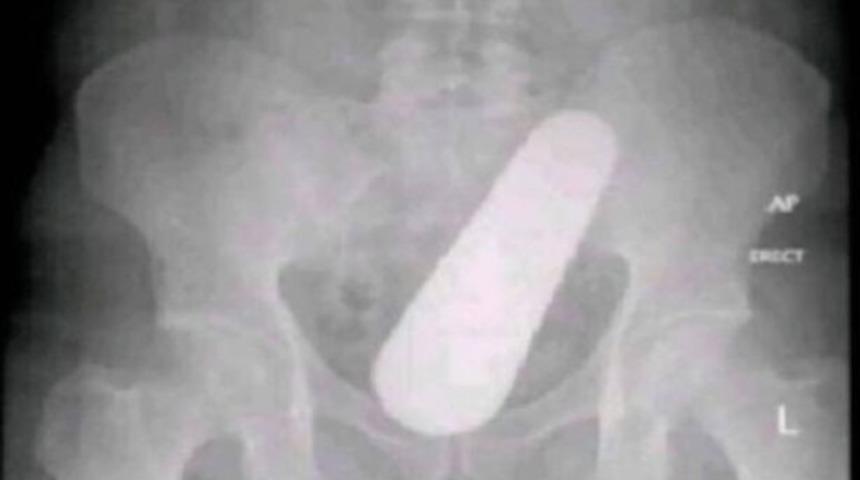

Kolombiya’da yaşayan ismi açıklanmayan 40 yaşındaki bir hasta ağrı şikayetiyle hastaneye gitti ve yürüyemediğini ancak rahatsızlığının nedenini bilmediğini söyledi. Doktorlar incelemelerine başladıklarında bir röntgende adamın renktumunun içinde büyük bir yabancı cisim buldular. Cerrahi operasyonla adamın rektumunda bulunan yabancı cisim alındı ve bunun bir salatalık olduğu keşfedildi.

Ameliyatın ardından kendisini tedavi eden doktorlara salatalığın nasıl oraya yerleştiğini bilmediğini söyledi. Evde çok fazla salatalık yediğini söyleyen adam, “Çok fazla yediğim için içimde büyüdü” diyerek doktorları şaşırttı. Adam teorisini salatalığın bir tohumunun sindirim sisteminde büyüdüğünü söyleyerek açıkladı. Doktorlar salatalığın kendiliğinden büyüme ihtimalinin olmadığını söyleyerek tedavisinin sonrasında hastayı taburcu etti.